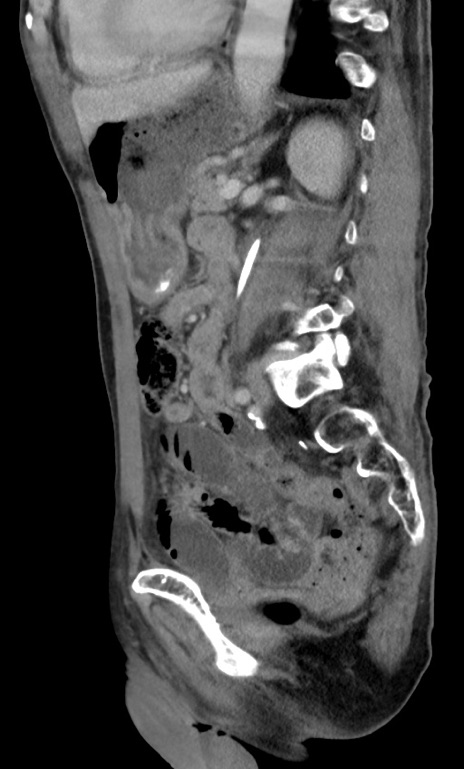

症例3(矢状断像)

【症例】 70歳代男性

【主訴】右鼠径部腫瘤、疼痛

【現病歴】本日朝より上記主訴あり、受診。

【既往歴】膀胱癌にて膀胱全摘、両側尿管皮膚瘻

【データ】WBC 5600、CRP 0.56